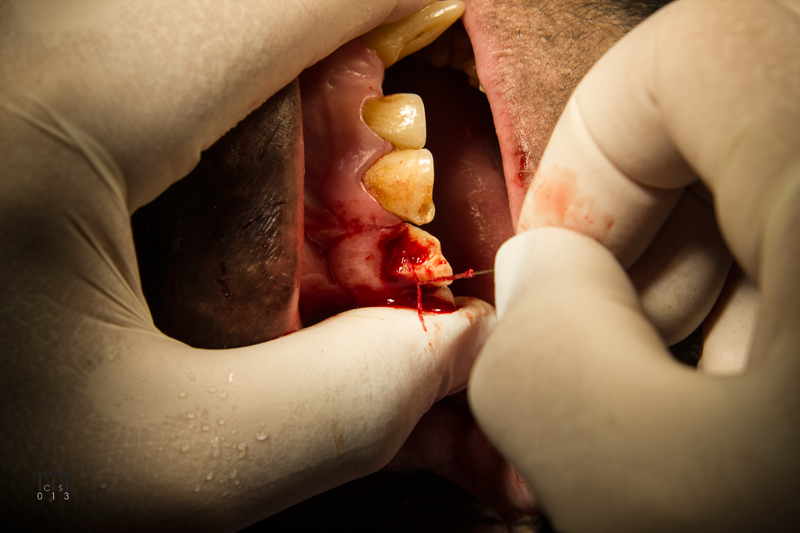

Bonobo Makanza: Extraction of two fractured incisors' residual roots

February, 2015Milwaukee County Zoo.Photos by Mark Scheuber, Zoo Keeper/Photographer

Maxillary left central incisor and lateral incisor residual roots. Region was inflamed, edematous prior to two weeks of antibiotic therapy.

Incision on crest of ridge.

Luxator technique utilized to remove residual roots.

556 surgical bur used to remove approximately 2mm. of alveolar bone surrounding each root ("ditching".)

Alveoli after roots extracted

Extracted roots

Simple interrupted sutures placed with knots inside the wound so that Makanza will find it difficult to disturb them with his fingers and tongue.